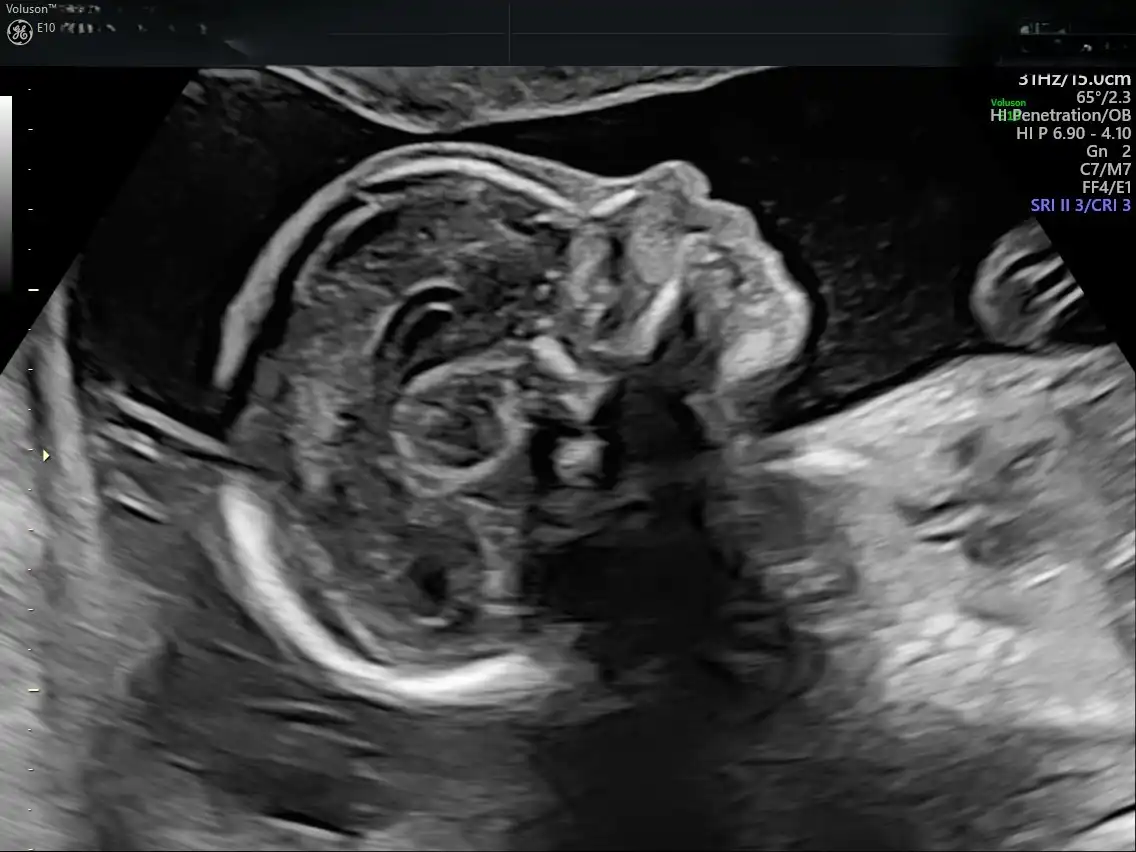

Το Voluson E10 BT19 αποτελεί την αιχμή της τεχνολογίας στην προγεννητική απεικόνιση, προσφέροντας εξαιρετική ευκρίνεια εικόνας, προηγμένη 3D/4D απεικόνιση και υψηλή ταχύτητα επεξεργασίας.

Με εξειδικευμένα εργαλεία για τον προγεννητικό έλεγχο και την καινοτόμο τεχνολογία HDlive™, επιτρέπει λεπτομερή και ρεαλιστική απεικόνιση του εμβρύου, ενισχύοντας τόσο τη διαγνωστική ακρίβεια όσο και την εμπειρία των γονέων.

Η χρήση αυτού του υπερηχογράφου είναι καθοριστική για την έγκαιρη ανίχνευση πιθανών ανατομικών ανωμαλιών και τη σωστή παρακολούθηση της κύησης, ενώ ταυτόχρονα προσφέρει μεγαλύτερη ασφάλεια και άνεση στη μητέρα και τον συνοδό της.